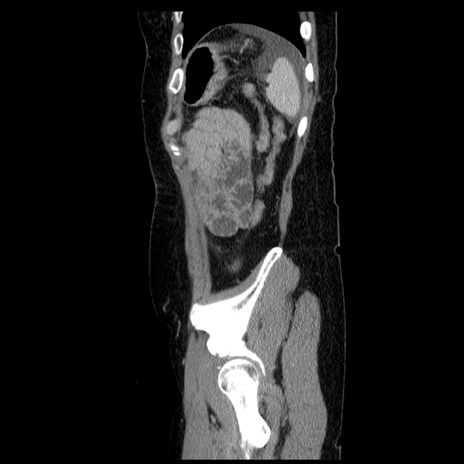

症例6(矢状断像)

【症例】50歳代女性

【主訴】下腹部痛

【既往歴】卵巣癌術後(8年前に当院で卵巣摘出)